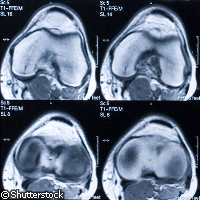

Una nueva técnica que aumenta la precisión de las imágenes por resonancia magnética (IRM) parece destinada a revolucionar tanto el ámbito de uso como la velocidad de esta herramienta de diagnóstico que es imprescindible en los escáneres de hospitales y laboratorios químicos. E...

Una nueva técnica que aumenta la precisión de las imágenes por resonancia magnética (IRM) parece destinada a revolucionar tanto el ámbito de uso como la velocidad de esta herramienta de diagnóstico que es imprescindible en los escáneres de hospitales y laboratorios químicos. Esta investigación, llevada a cabo en la Universidad de York (Reino Unido) y publicada en Internet por la revista Science, consistió en la manipulación de parahidrógeno. Para desarrollar la nueva técnica, los investigadores utilizaron parahidrógeno (el combustible de las lanzaderas espaciales) e iniciaron una interacción reversible con una estructura molecular diseñada para este fin. Ésta transfirió su magnetismo a una serie de moléculas, facilitando de este modo su detección hasta un punto antes imposible. Es la primera vez que se utiliza el parahidrógeno con este propósito. La nueva tecnología supone un avance importante para la investigación científica, ya que reducirá drásticamente el tiempo necesario para la obtención de resultados con la técnica de resonancia magnética nuclear (RMN). La RMN es hoy en día la técnica más utilizada en el campo de la química para obtener información analítica y estructural. El equipo de investigadores consiguió aumentar la precisión de la RMN más de mil veces. Así, los datos que antes se tardaba noventa días en registrar ahora se pueden conseguir en cinco segundos, y las imágenes de RMN se pueden obtener en una fracción de segundo en lugar de en más de cien horas. Del mismo modo, esta tecnología aplicada al diagnóstico de pacientes permitirá a los médicos detectar muchas más enfermedades en menos tiempo. Según el profesor Gary Green, del Departamento de Psicología de la Universidad de York y director del Centro de Neurorradiología de York, «el nuevo método ayudará a los médicos a diagnosticar con más precisión y rapidez un amplio espectro de enfermedades.» «Esta técnica podría llegar a sustituir a las herramientas de diagnóstico por imagen que emplean sustancias radiactivas o metales pesados y que pueden provocar problemas de salud.» La nueva técnica revolucionará el diagnóstico por imagen, y su mayor calidad beneficiará a las personas que padezcan cáncer o traumatismos o utilicen prótesis ortopédicas. El profesor Simon Duckett, del Departamento de Química de la Universidad de York y director del Centro de Resonancia Magnética, afirmó que «este adelanto permitirá utilizar las técnicas de RMN para ahondar en nuestros conocimientos de las funciones fundamentales de los sistemas biológicos.» Esta tecnología ya se está desarrollando para su posterior uso comercial. Según un portavoz de Bruker BioSpin, empresa que desarrolla herramientas de espectroscopia por RMN y de investigación preclínica con IRM, «esta tecnología podría revolucionar las técnicas de RMN y IRM en muy poco tiempo.»